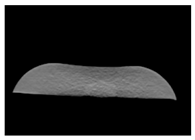

| CT-scan |  |  |  |

| CT-scan |  |  |  |

| CT-scan |  |  |  |

| CT-scan |  |  |  |

| CT-scan |  |  |  |

| CT-scan |  |  |  |